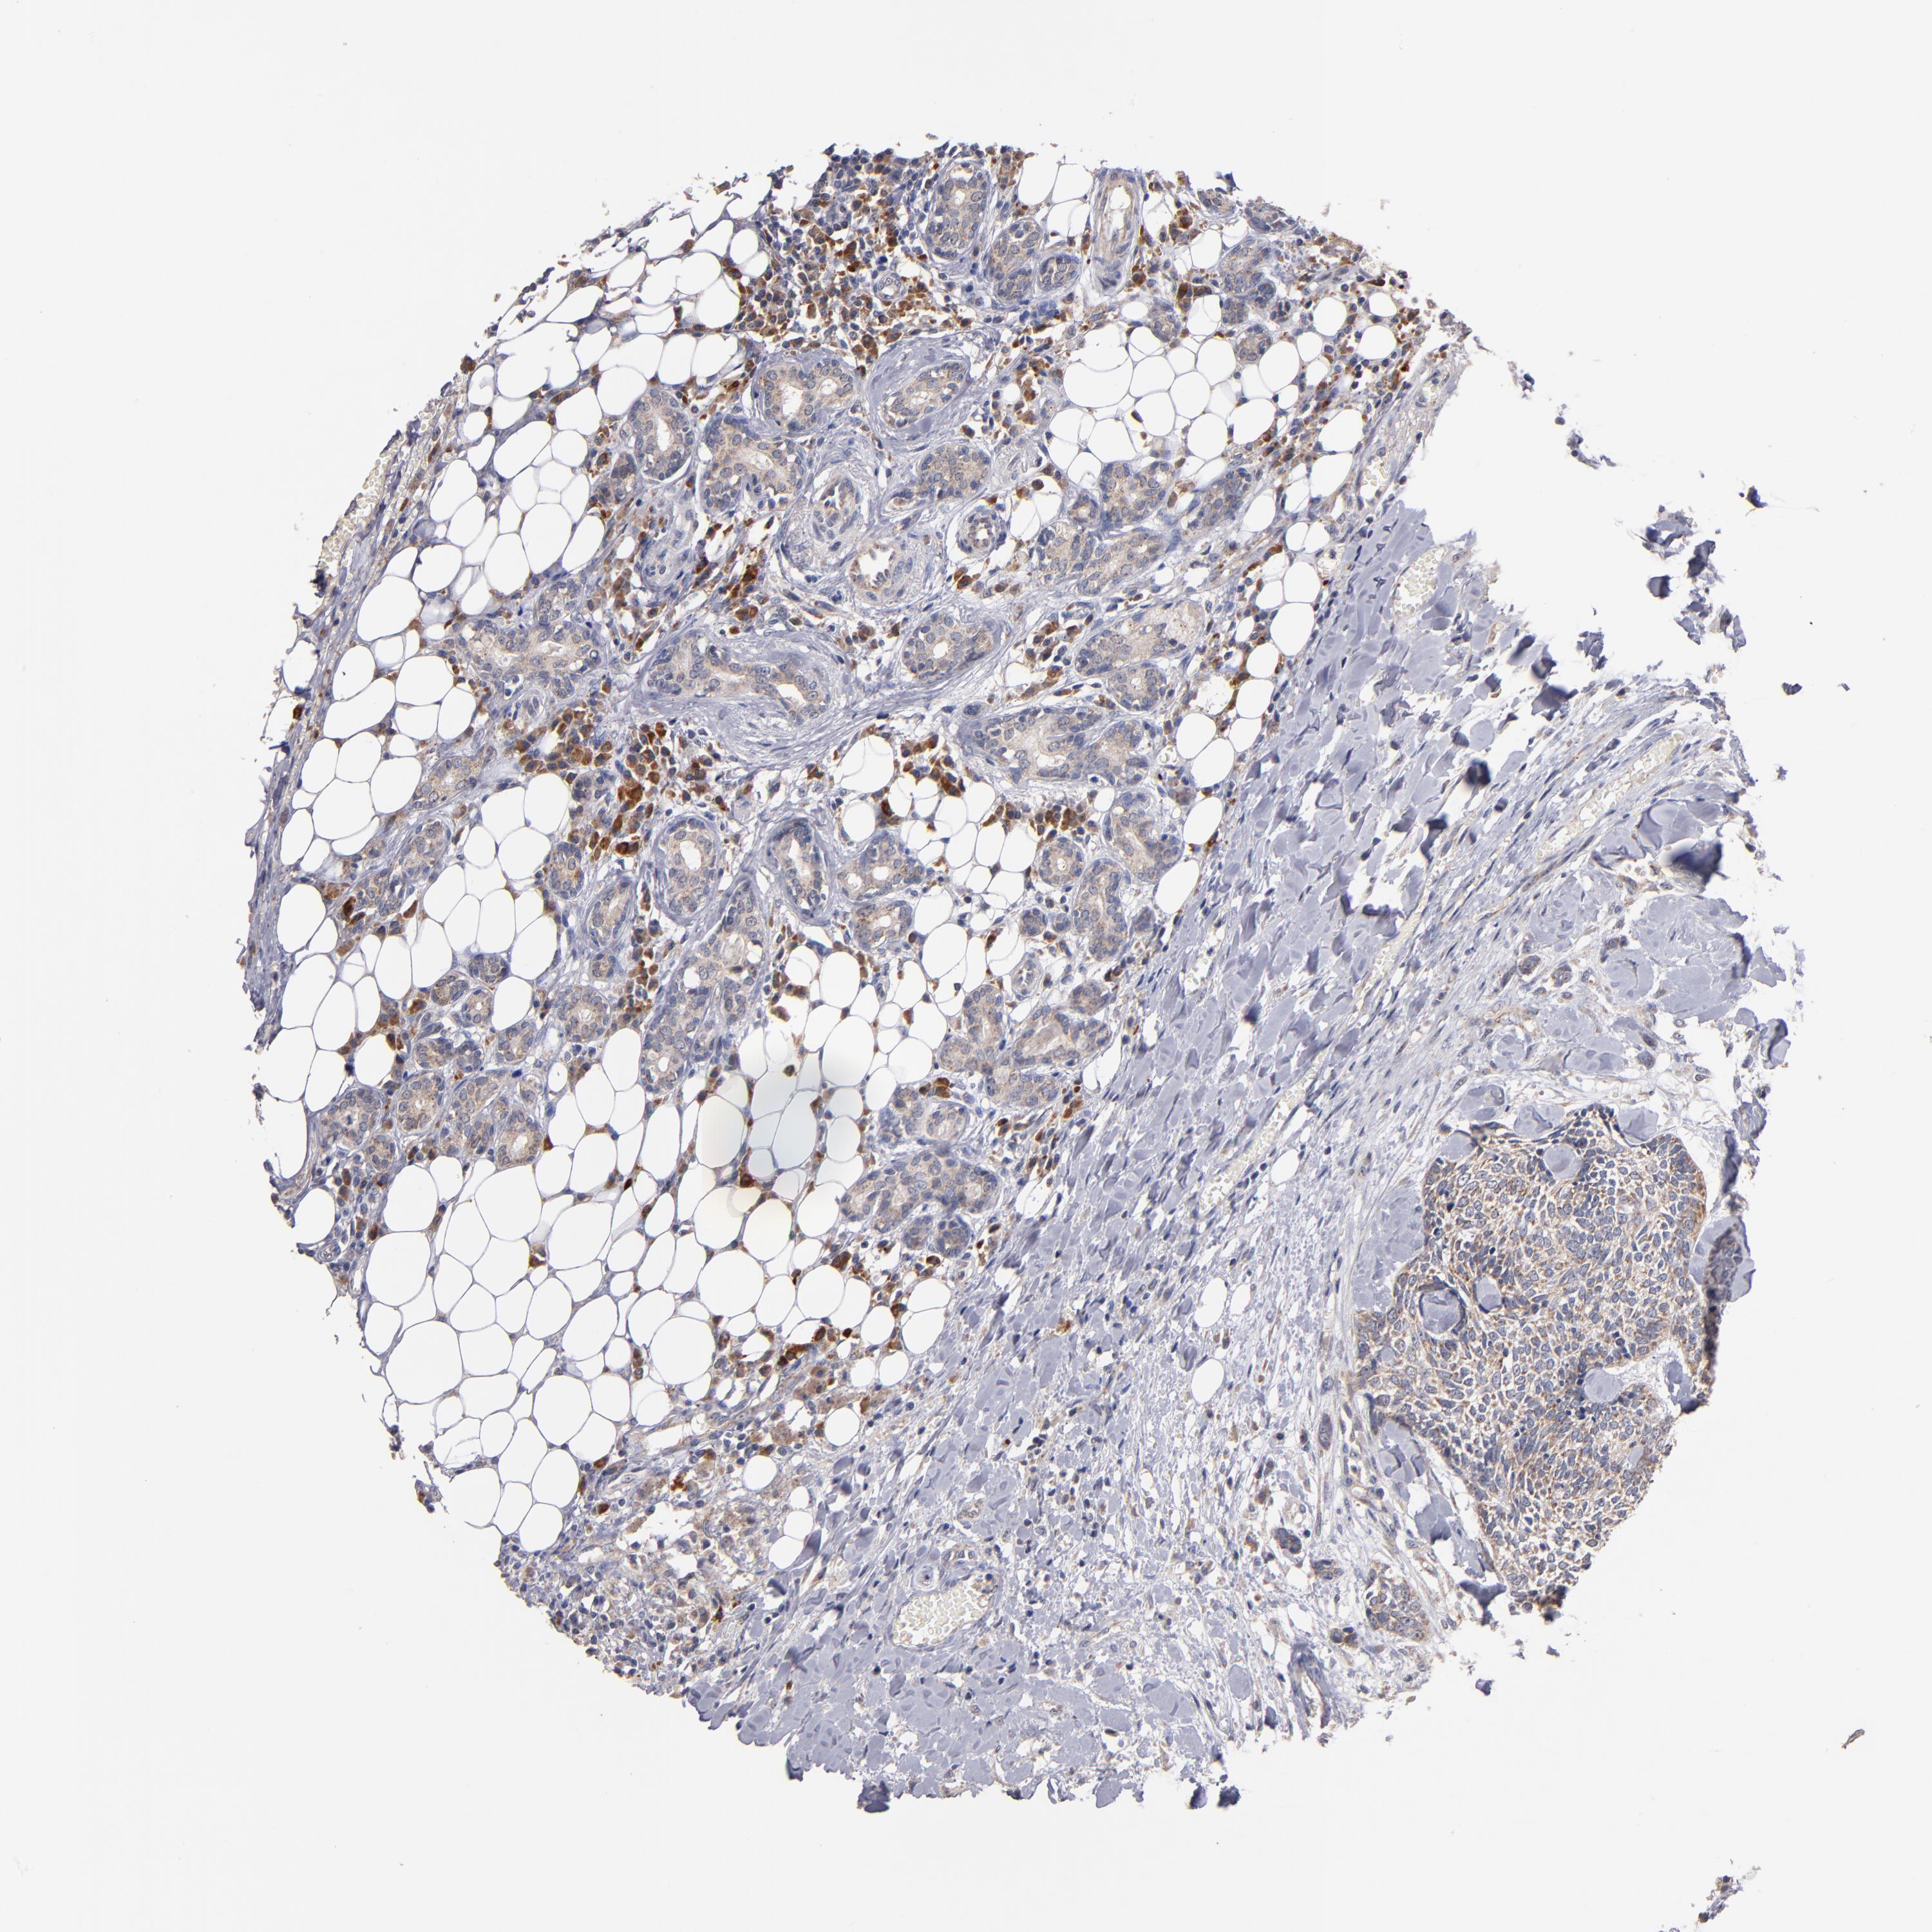

HEAD AND NECK CANCER - Protein expressioni

A mouse-over function shows sample information and annotation data. Click on an image to view it in a full screen mode. Samples can be filtered based on level of antibody staining by selecting one or several of the following categories: high, medium, low and not detected. The assay and annotation is described here.

Antibody stainingi

Antibody staining in the annotated cell types in the current human tissue is reported as not detected, low, medium, or high, based on conventional immunohistochemistry profiling in selected tissues. This score is based on the combination of the staining intensity and fraction of stained cells.

Each image is clickable and will lead to virtual microscopy that enables deeper exploration of all samples and also displays staining intensity scores, fraction scores and subcellular localization as well as patient and tissue information for each sample.

Antibody CAB003857

Staining

High

Medium

Low

Not detected

Intensity

Strong

Moderate

Weak

Negative

Quantity

>75%

75%-25%

<25%

None

Location

Nuclear

Cytoplasmic/membranous

Cytoplasmic/membranous,nuclear

Squamous cell carcinoma, metastatic, NOS